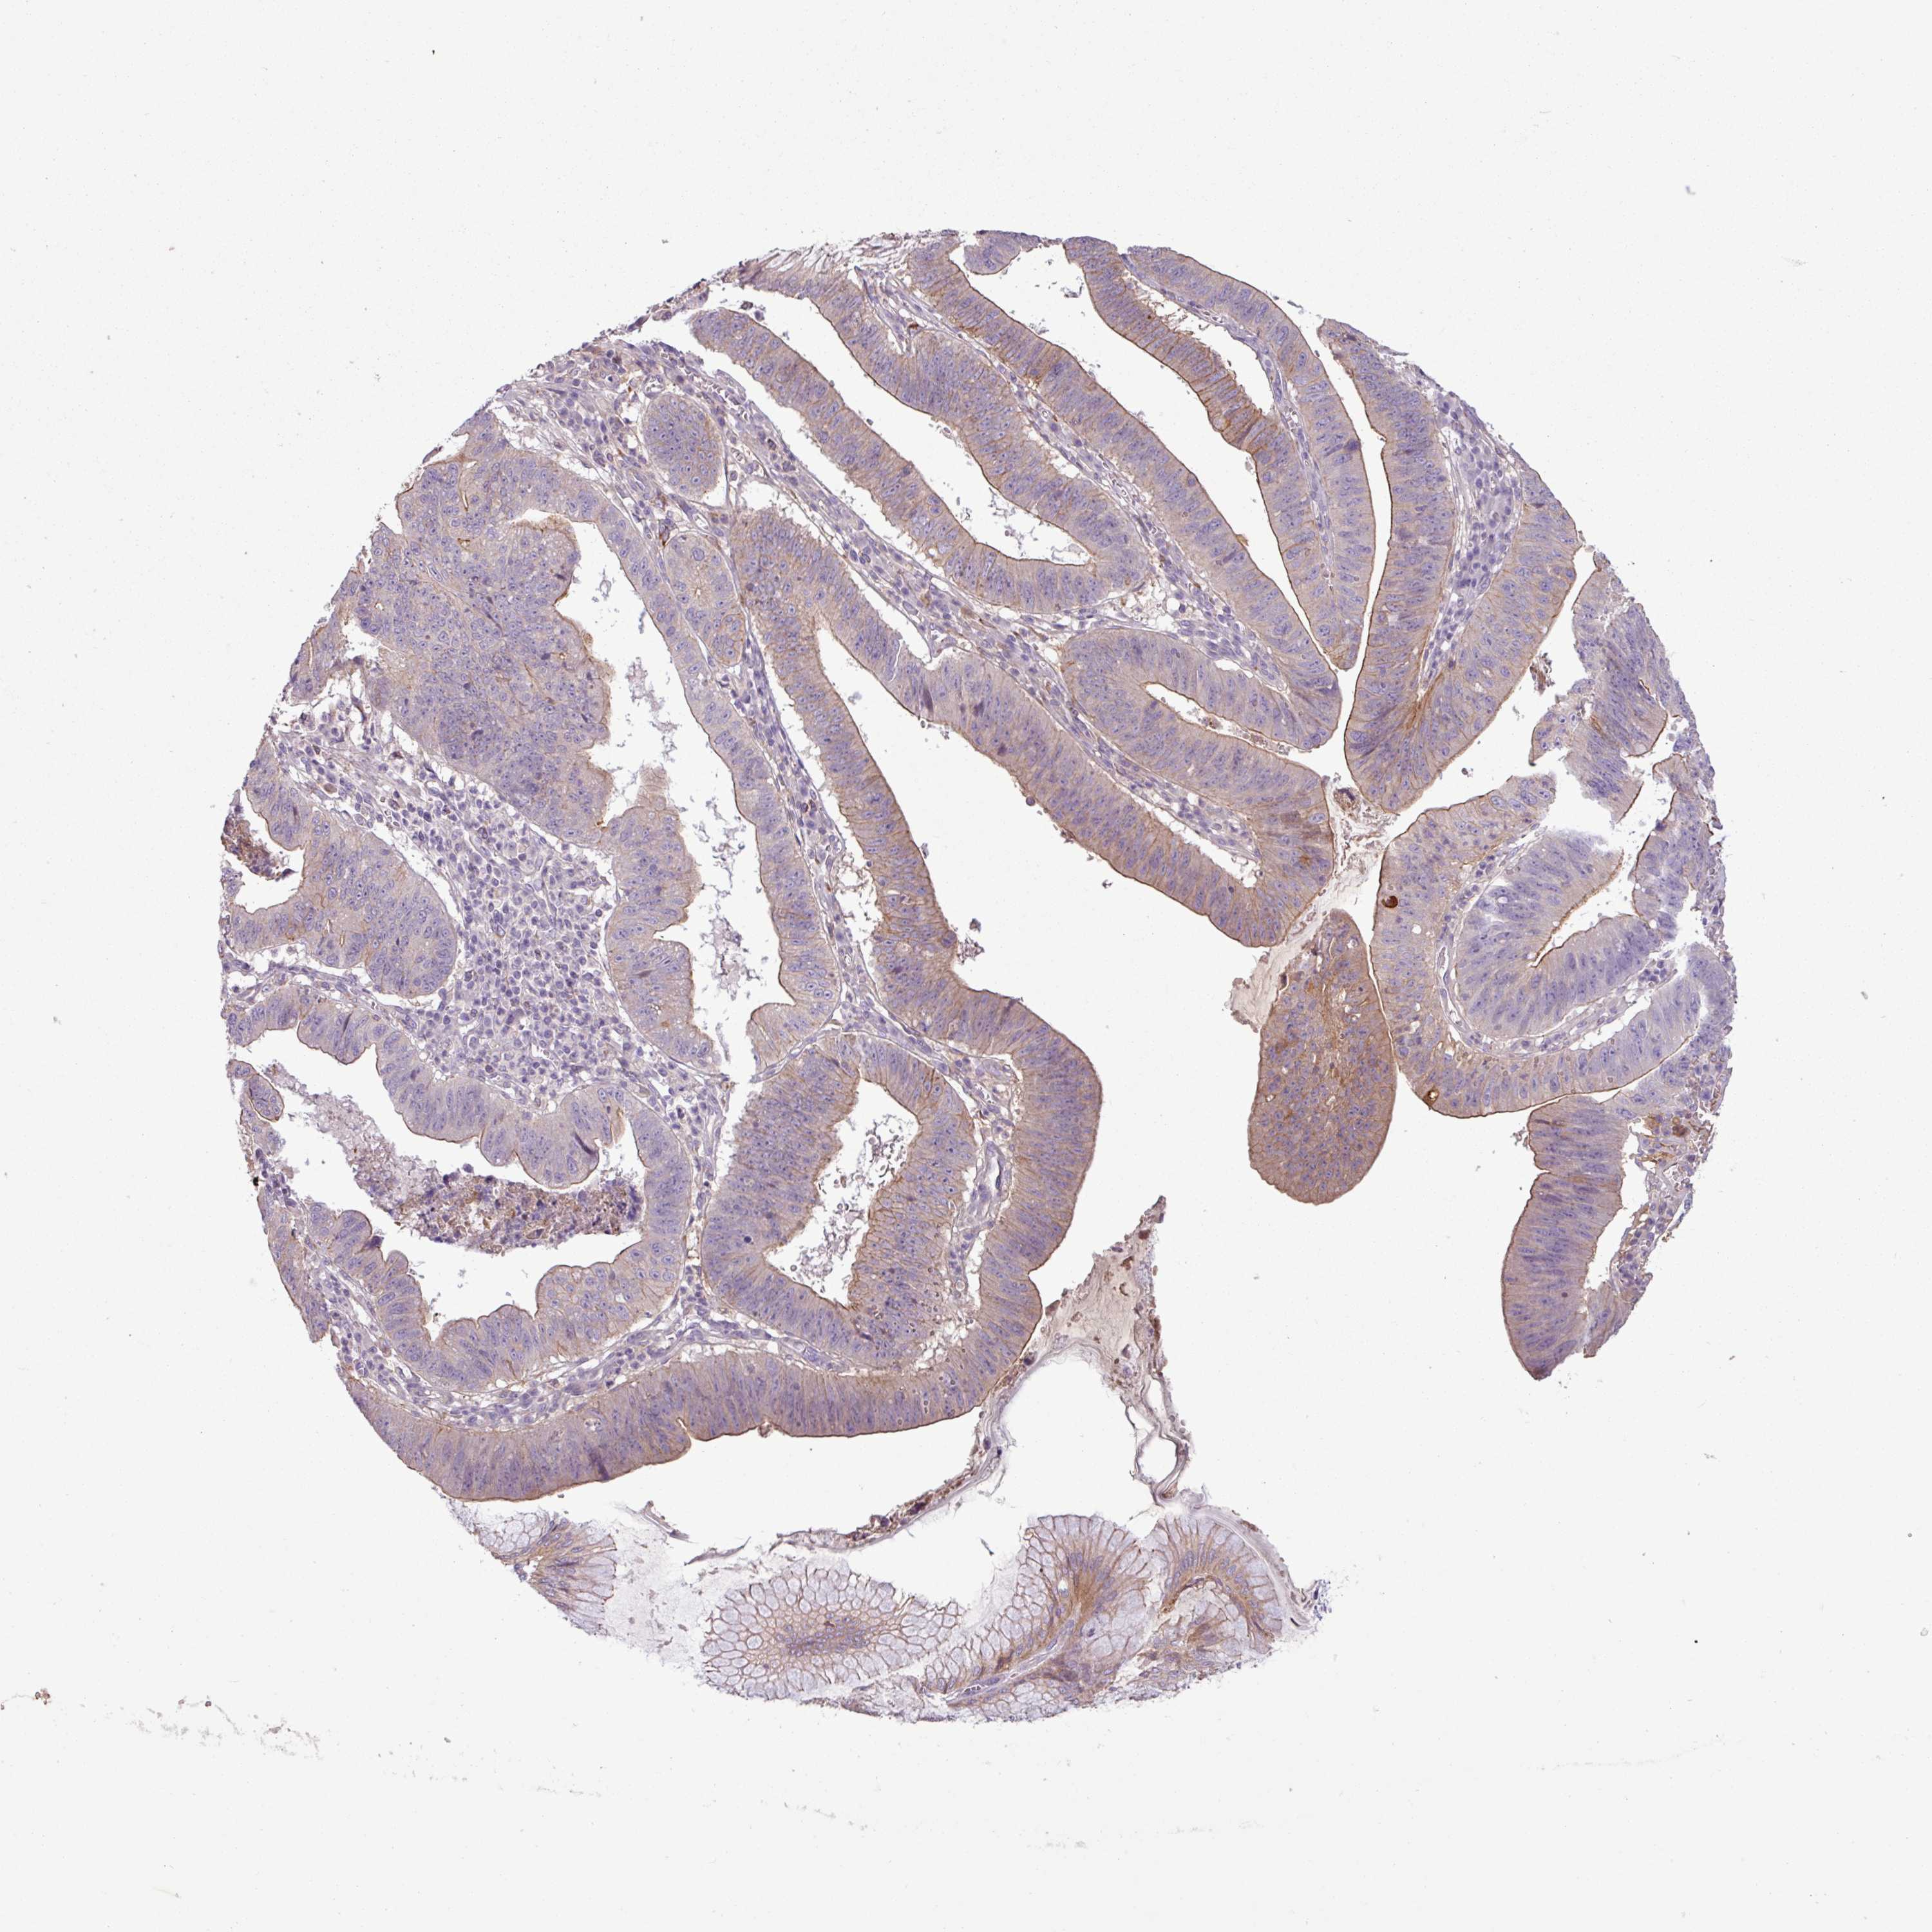

STOMACH CANCER - Protein expressioni

A mouse-over function shows sample information and annotation data. Click on an image to view it in a full screen mode. Samples can be filtered based on level of antibody staining by selecting one or several of the following categories: high, medium, low and not detected. The assay and annotation is described here.

Note that samples used for immunohistochemistry by the Human Protein Atlas do not correspond to samples in the TCGA dataset.

Antibody stainingi

Antibody staining in the annotated cell types in the current human tissue is reported as not detected, low, medium, or high, based on conventional immunohistochemistry profiling in selected tissues. This score is based on the combination of the staining intensity and fraction of stained cells.

Each image is clickable and will lead to virtual microscopy that enables deeper exploration of all samples and also displays staining intensity scores, fraction scores and subcellular localization as well as patient and tissue information for each sample.

HPA046356

Staining

High

Strong

>75%

Cytoplasmic/membranous

Adenocarcinoma, NOS